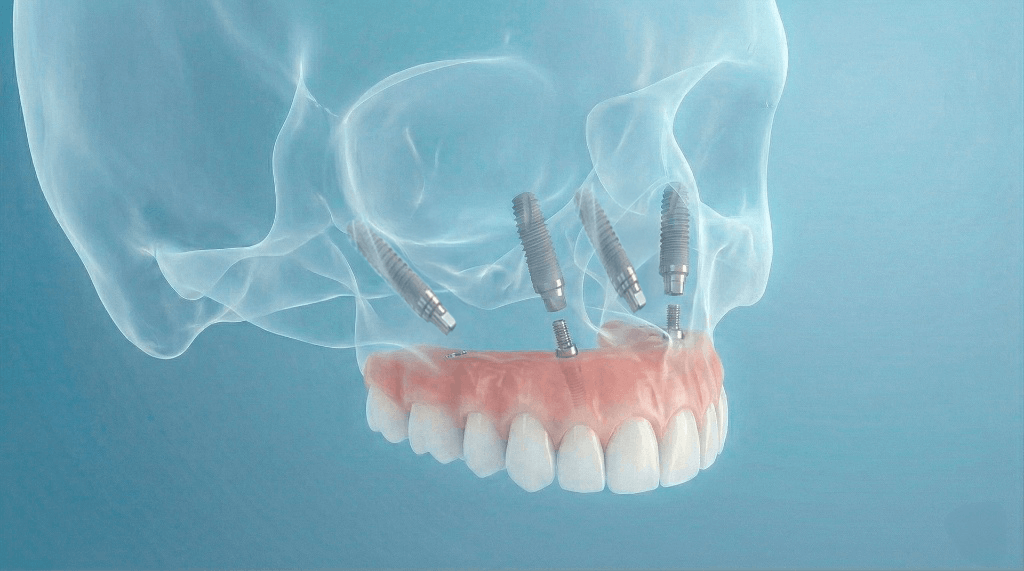

Metoda All-on-4 to zaawansowane rozwiązanie protetyczne, które pozwala na pełną rekonstrukcję łuku zębowego przy użyciu zaledwie czterech implantów. Jest to sprawdzona droga do odzyskania stałego uzębienia, szczególnie polecana pacjentom zmagającym się z zanikiem kości w żuchwie.

System ten opiera się na precyzyjnym rozmieszczeniu czterech punktów podparcia, które utrzymują cały most protetyczny:

Dwa implanty centralne

Wprowadzane równolegle do siebie (zazwyczaj w miejscach „dwójek”).

Dwa implanty boczne

Wprowadzane pod kątem około 20 stopni (w miejscach „czwórek” lub „piątek”).

Zastosowanie kąta nachylenia pozwala na optymalne wykorzystanie dostępnej tkanki kostnej, co często eliminuje konieczność przeprowadzania skomplikowanych zabiegów jej odbudowy.